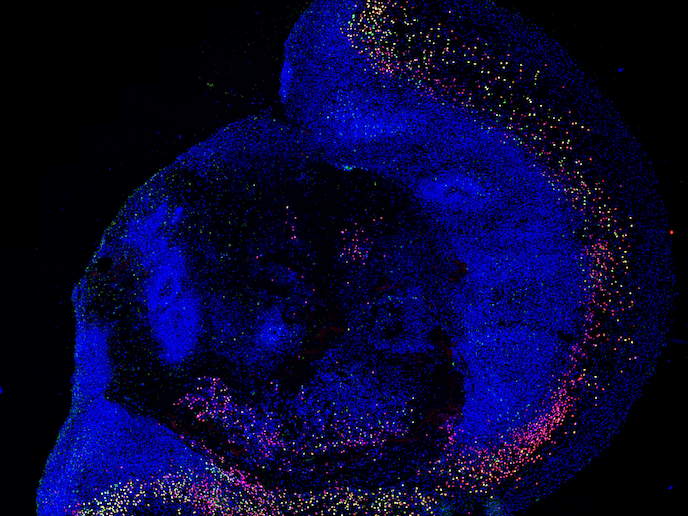

Les organoïdes cérébraux constituent de solides modèles 3D pour l’étude du neurodéveloppement chez l’humain

Le fait que les chercheurs ne disposent pas d’un accès direct au tissu cérébral humain permettant d’étudier l’autisme(s’ouvre dans une nouvelle fenêtre) et d’autres troubles du neurodéveloppement aux niveaux moléculaire et cellulaire, constitue un obstacle à une meilleure compréhension de ces pathologies. Une dépendance aux modèles animaux s’est ainsi installée, mais ces derniers ne sont pas totalement comparables aux humains. Toutefois, le projet ProTeAN, soutenu par le programme Actions Marie Skłodowska-Curie(s’ouvre dans une nouvelle fenêtre), a pu bénéficier des récentes découvertes en matière d’utilisation de cellules souches pour créer des modèles 3D appelés organoïdes. Les organoïdes sont capables d’imiter le développement du cerveau humain. Ils sont également en mesure d’acquérir des fonctions cérébrales développées, comme la formation de réseaux neuronaux activés. L’équipe a produit ses organoïdes cérébraux à partir de cellules souches dentaires, prélevées sur des dents de lait ou de sagesse. «Ce modèle nous amène à penser que nous sommes en bonne voie pour mieux comprendre la biologie humaine des troubles du neurodéveloppement», déclare Catarina Seabra. Rattachée à l’hôte du projet, le Centre de neurosciences et de biologie cellulaire(s’ouvre dans une nouvelle fenêtre) de l’université de Coïmbre, au Portugal, elle est également boursière de ce projet. L’équipe a mis en place la première biobanque de cellules souches dentaires au Portugal en vue de l’étude des troubles cérébraux. Elle a obtenu l’approbation déontologique de l’hôpital pédiatrique et de l’université de Coïmbre. Cette approbation a permis à l’équipe de reprogrammer les cellules afin de s’assurer de leur capacité à devenir virtuellement n’importe quel type de cellule, soit des cellules dites pluripotentes. La biobanque contient des cellules souches dentaires qui ont été collectées au sein de groupes de patients autistes et de groupes de contrôle. Ces cellules avaient déjà constitué une ressource vitale pour le projet Syn2Psy, financé par l’UE. L’équipe a été interrogée par des chaînes de télévision nationales, telles que RTP(s’ouvre dans une nouvelle fenêtre) (site web en portugais) et SIC(s’ouvre dans une nouvelle fenêtre) (site web en portugais). Ces programmes ont touché une audience de plus d’un million de spectateurs au Portugal.

Des cellules souches dentaires aux organoïdes cérébraux

L’objectif de ProTeAN était de créer des organoïdes cérébraux qui permettraient aux neurones, les éléments de base du cerveau, de croître dans un environnement 3D et de former les structures complexes que l’on retrouve chez les humains. La composition de l’organoïde, de même que les propriétés neuronales telles que la complexité et la communication pouvaient ensuite faire l’objet de tests en laboratoire. La comparaison entre les échantillons de patients et les échantillons de contrôle est susceptible de faire apparaître les altérations qui se produisent au cours du développement neuronal ou de la communication dans le cadre de l’autisme. Pour garantir leur pertinence, les cellules souches dentaires ont été caractérisées par cytométrie en flux(s’ouvre dans une nouvelle fenêtre), une technique permettant d’identifier les protéines à la surface des cellules, et par RT-PCR quantitative(s’ouvre dans une nouvelle fenêtre), une méthode employée pour détecter les protéines codées par des gènes. Ces cellules ont ensuite été induites pour devenir des cellules souches pluripotentes et être utilisées pour créer les organoïdes cérébraux 3D. «Nous avons constitué des calendriers stratégiques afin de mieux comprendre les étapes majeures du développement des organoïdes. Nous avons appris que les organoïdes cérébraux expriment des marqueurs neuronaux développés au bout de trois mois. Cela montre leur potentiel en tant que solides modèles de neurodéveloppement. Mais nous n’avons constaté une activité électrique complexe que dans les organoïdes âgés de six mois», ajoute Catarina Seabra.